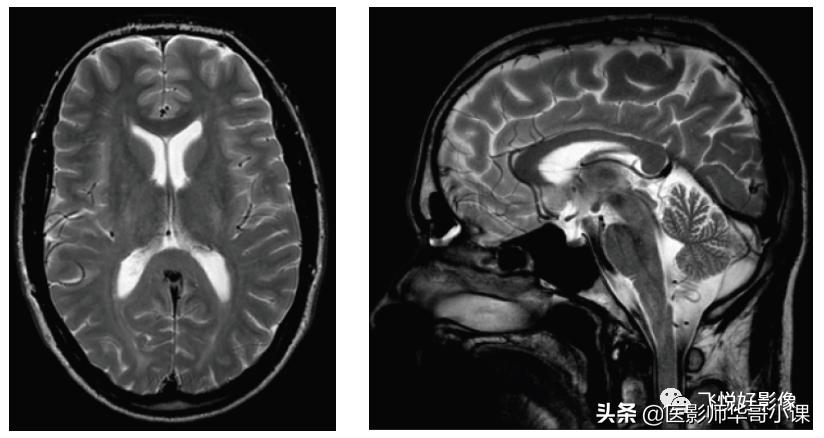

我们通过磁共振脑实质成像,来表现不同加权图像的信号对比特点,通过短TR、短TE实现T1加权成像;通过长TR、长TE实现T2加权成像(由于SE采集效率低,在实现T2加权中,可利用快速自旋回波序列TSE代替);通过长TR、短TE实现PD加权成像。

图3,TSE T2加权图像。左图为横断面脑实质T2加权图像,TR=3502ms,TE=120ms;右图为矢状面T2加权图像。T2加权图像利用长TR、长TE来实现。在长TR的情况下,扫描周期内纵向磁化矢量已充分恢复。采用长的TE后,T1效应进一步排除,主要反映组织间横向弛豫的差异。长TE的另一作用是突出液体等横向弛豫较慢的组织之信号。一般病变部位都会出现大量水的聚集,用T2加权像可以非常满意地显示这些水的分布。因此,T2加权像在确定病变范围上有重要作用。T2加权图像中,脑灰质相对于脑白质显示为稍高信号;脑脊液在T2加权图像中为高信号,而骨结构、空气等在磁共振中不产生信号,而皮下脂肪组织、骨髓脂肪组织在脂肪抑制的条件下显示为低信号。(图像源自飞利浦磁共振系统)